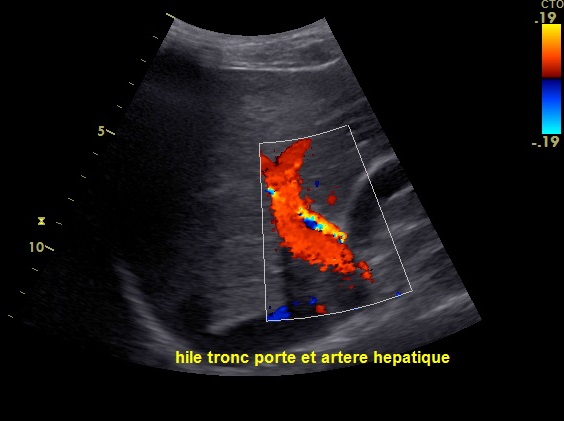

Coupe intercostale de

la ligne axilaire anterieuse droit ( long sagitale -

vesiculaire ) avec technique de encoder de la

difference vitesse du flux sanguine , artere

hepatique est en vue tres nette paralellique au

dessus de la branche droit de la veine porte .

Sa diametre est moins de 5mm |

Flux de artere hepatique est

alternative systole - diastole |